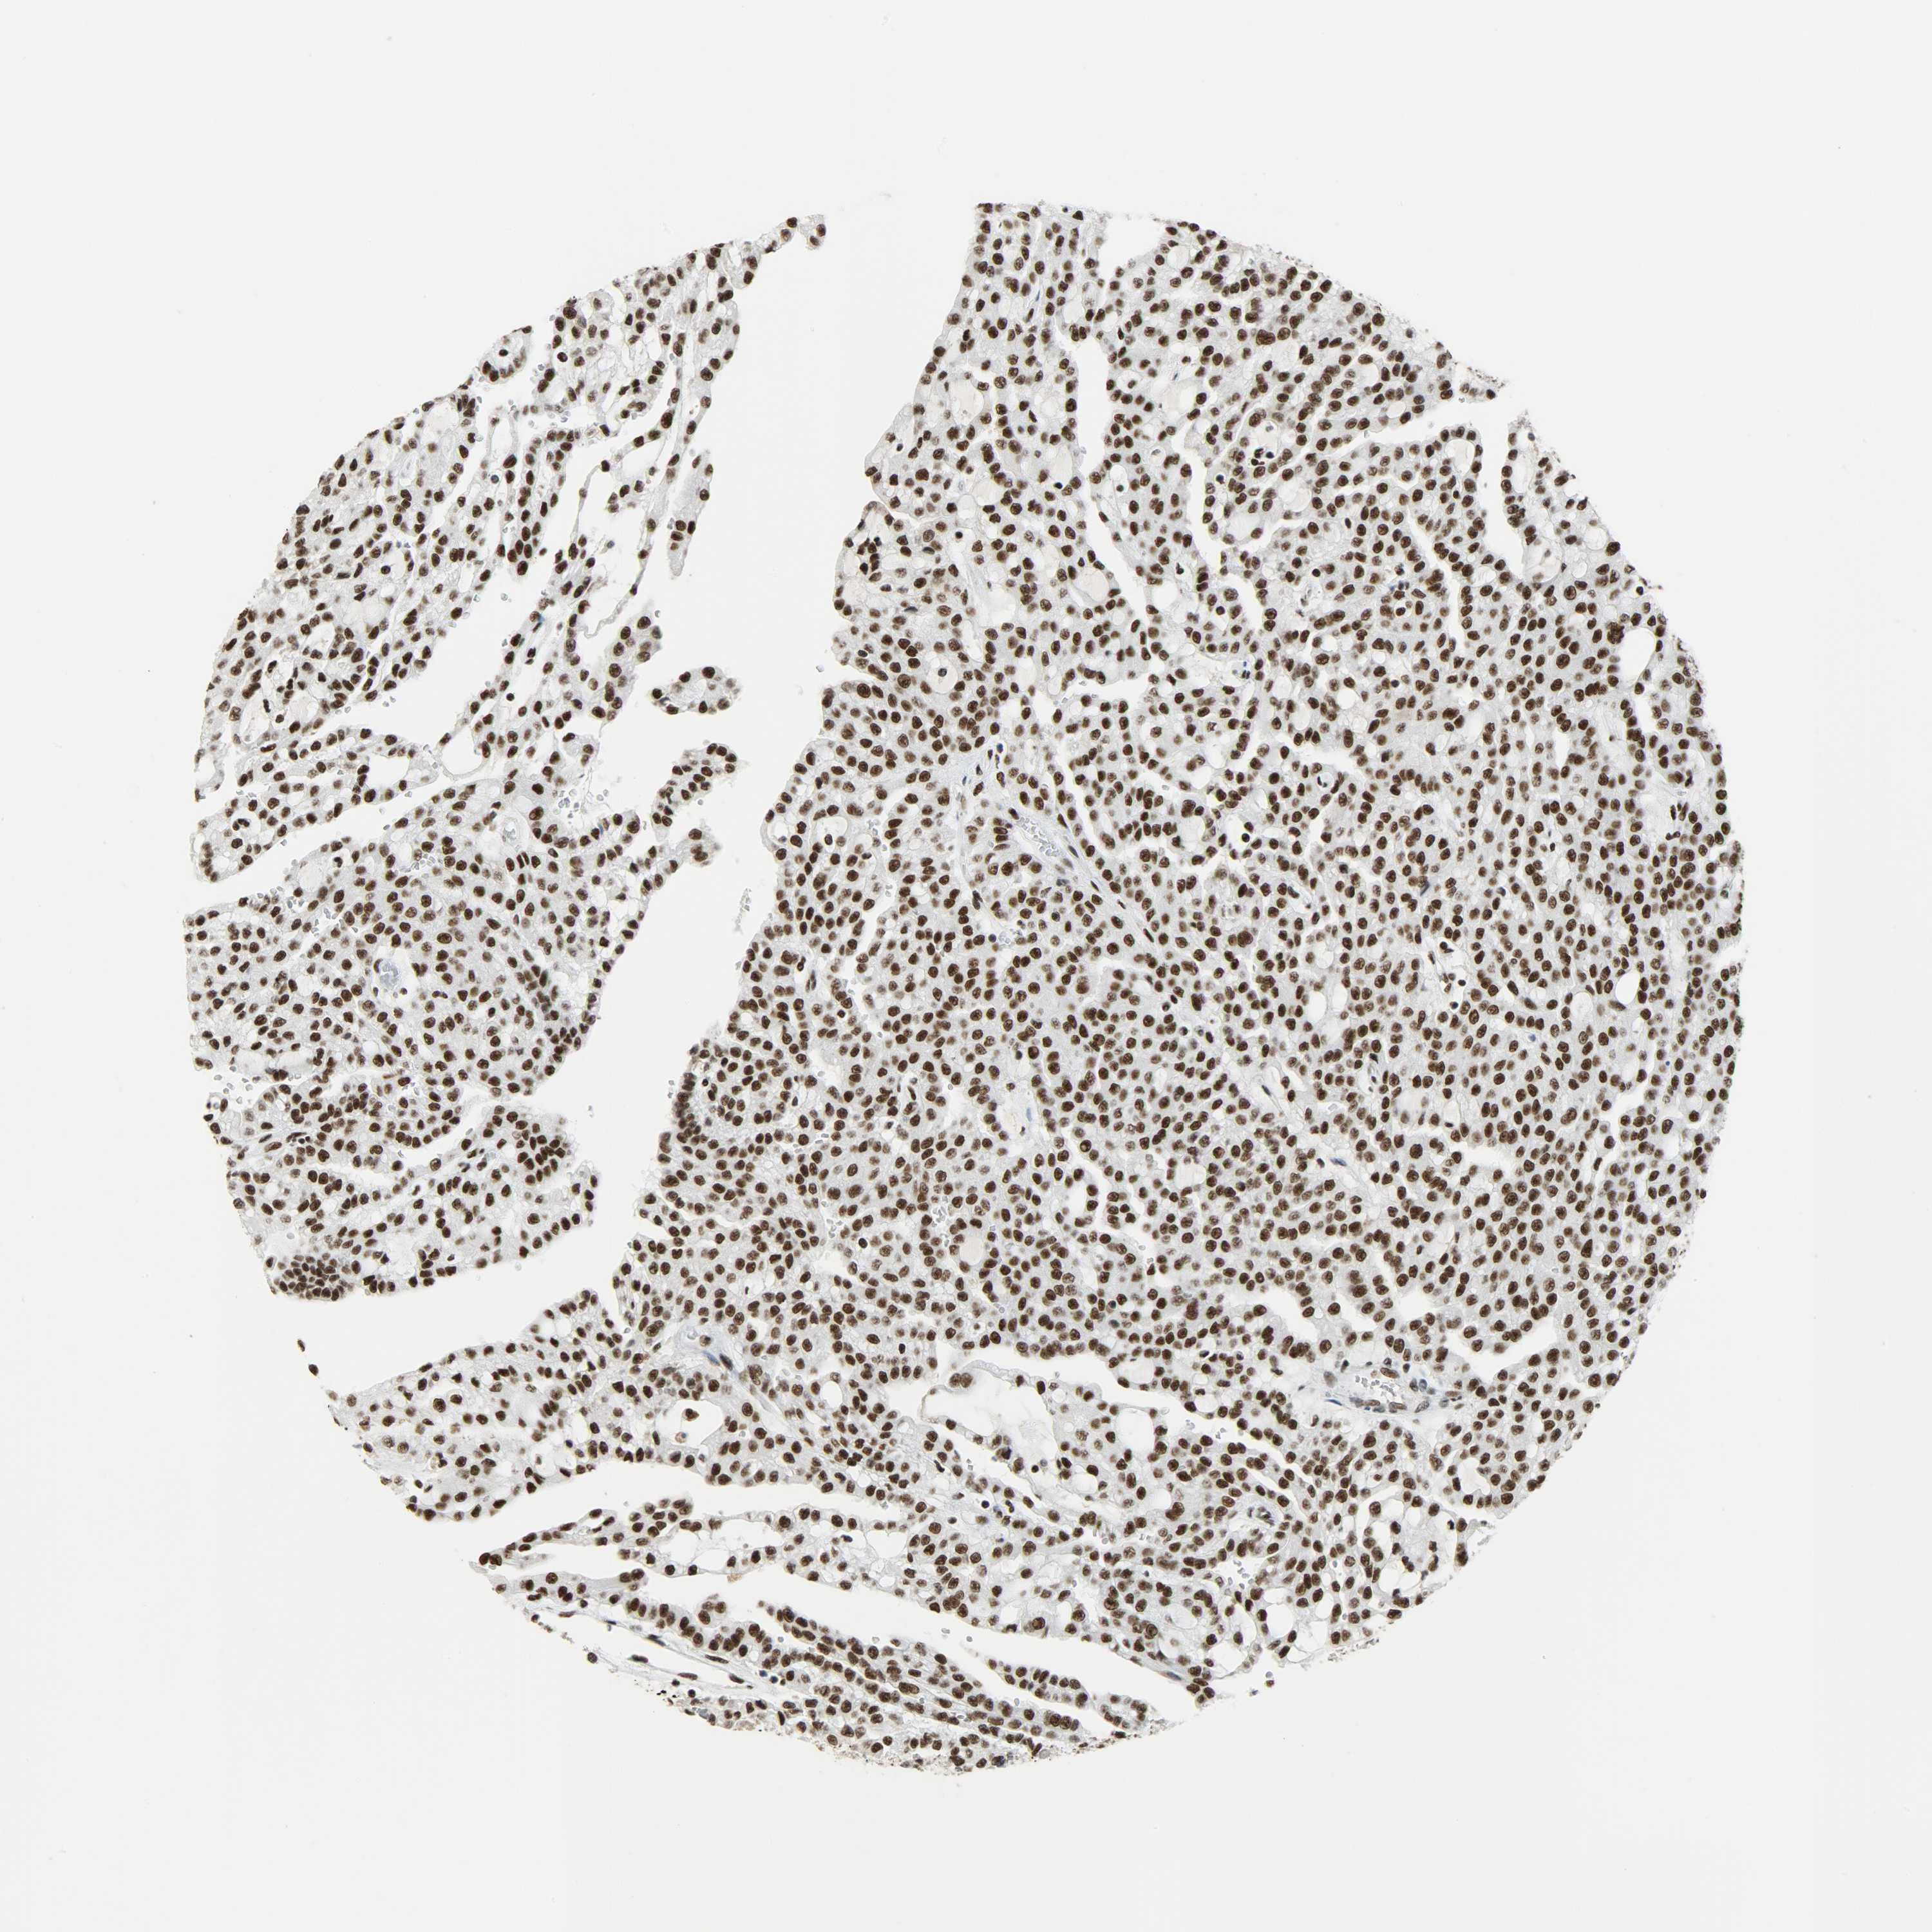

SSB is potential prognostic, high expression is unfavorable in Kidney Renal Papillary Cell Carcinoma (TCGA)